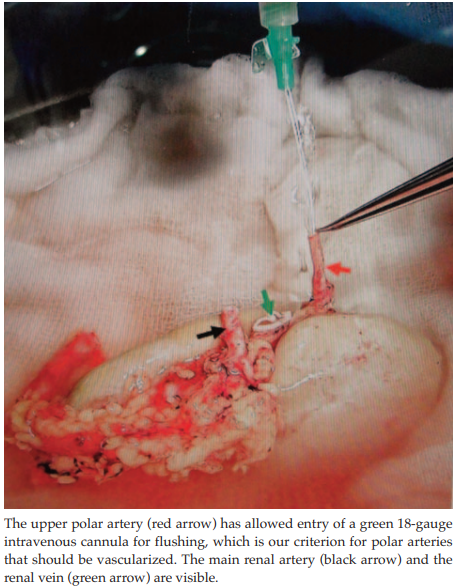

Donor kidneys are placed retroperitoneally in the right iliac fossa for end-to-side anastomosis of the main renal vessels to the external iliac vessels with running 6/0 polypropylene sutures. The IEA is dissected to gain extra length in anticipation of revascularizing the UPA (Figure 1), which is also prepared for this anastomosis. The UPA is deemed implantable only if its lumen admits an 18-gauge green intravenous cannula that can demonstrate successful hydrodilation (Figure 2). The implantation strategy is to place the kidney upside down with the ureter cephalad so that the upper pole becomes the lower pole, to lie near the IEA. Clamps are removed after the end-to-side vascular anastomosis to the external iliac vessels is completed, which allows perfusion of the bulk of the graft, except for the area supplied by the UPA. Next, the UPA is anastomosed end-to-end to the IEA with interrupted 7/0 polypropylene sutures to achieve global perfusion (Figure 3). The ureter is then implanted using the extravesical technique and stented.

Transplant of allografts with multiple renal arteries is technically more demanding because of increased risk of vascular and ureteral complications.9 A recent meta-analysis has shown an increased risk of delayed graft function and a decreased 1-year graft survival compared with single renal artery allografts.10 There is consensus on using the IEA for revascularization of LPAs, primarily to preserve ureteric blood supply, but ligation of UPAs and loss of ±10% parenchyma has been traditionally acceptable.5,9,11 The use of the IEA for revascularization of LPAs is convenient because of the natural anatomic proximity. The same proximity can be achieved for UPAs by upside-down placement of the kidney, with the ureter cephalad, which converts a UPA into an LPA. With the UPA in this position, it can be anastomosed easily to the IEA without clamps on the EIA. This so-called “off-clamp” UPA revascularization does not increase the RWT and therefore does not hinder initial graft function, and all of our cases presented here have demonstrated this success. We used a simple and practical method to choose the proper size of polar artery for revascularization; that is, all arteries that admit an 18-gauge green intravenous cannula are revascularized (Figure 2).

Figure 2. Cold Flushing of Donor Kidney